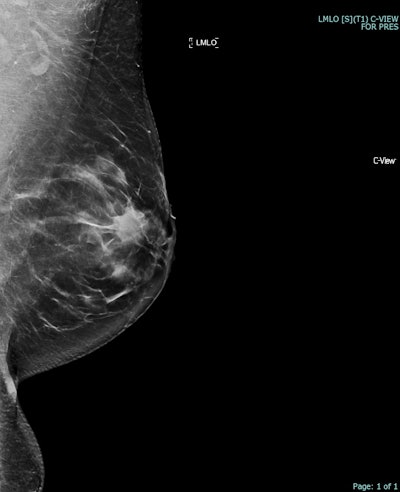

Correlative mammographic, sonographic, and histopathological findings in a 37-year-old woman presenting with a left breast skin abnormality and palpable mass. (a) Synthesized 2D mammogram, left breast, mediolateral oblique (MLO) projection: Spiculated mass density in the upper outer quadrant.Courtesy Atienza-Hipolito and Alderman; RANZCR